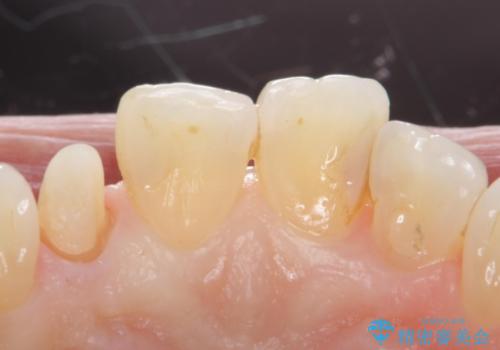

- 右上の前歯が取れたとのことで来院された患者様です。

再根管治療からのやり直しをご提案しましたが、ご希望されなかったため土台(コア)のやりかえからとなりました。

- 右上2 仮歯/11,000円 ファイバーコア/22,000円 ジルコニアクラウン(スペシャル)/154,000円 合計187,000円費用は治療当時の料金となります